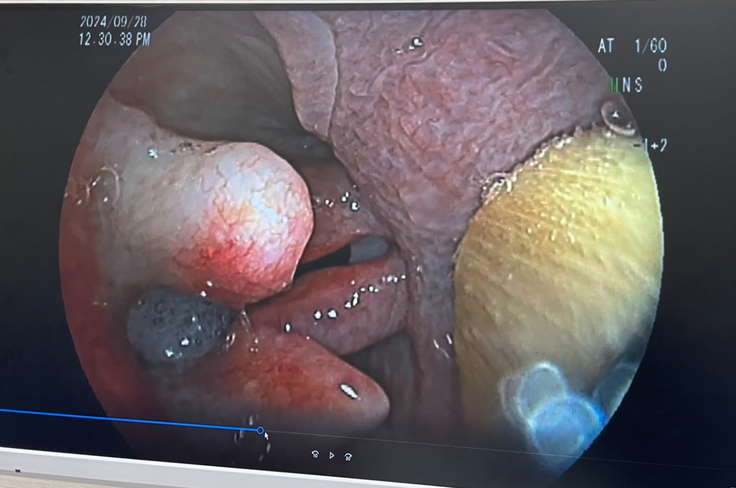

2024年9月15日〜28日

当初診察していただいていた病院Aから循環器の専門病院Bを紹介いただき、レントゲン、エコー、内視鏡検査などを行った結果、僧帽弁閉鎖不全を発症しており、心臓からの血液逆流は見られるが、症状は軽微なもので肺水腫に至るようなレベルではなく、今回の不調は喉の異常が原因で喉頭麻痺という病気の診断を受けました。

※掲載許可取得済み

内科治療として、ステロイドを投薬し、運動制限と興奮を避ける保存療法で騙し騙し生活を続けることはできるが症状が改善することはなく、外科的治療で気管の入り口を開くため、のどの側面から喉頭へアプローチし、喉頭を構成する軟骨同士を結びつけ、喉頭内腔を拡げる「披裂軟骨側方化術(タイバック)」という手術を勧めていただきました。